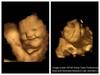

Folic Acid: గర్భిణులకు ఫోలిక్ యాసిడ్ ఎందుకు అత్యవసరం? ఫోలిక్ యాసిడ్ తగ్గితే ఏమవుతుంది?